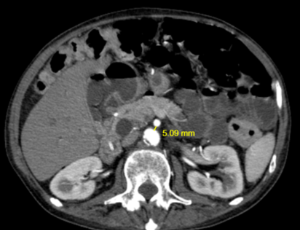

Superior mesenteric vein syndrome: A rare cause of duodenal obstruction mimicking SMA syndrome – Case report and surgical management

Background: Superior Mesenteric Vein (SMV) syndrome is an extremely rare cause of duodenal obstruction, resulting from external compression of the third portion of the duodenum by the SMV against the aorta. Due to its rarity and clinical similarity to Superior Mesenteric Artery (SMA) Syndrome, SMV syndrome may be misdiagnosed.

J Clin Exp Gastroenterol, 2025, Volume Volume 4, Issue Issue 1, p7-10 | DOI: 10.46439/gastro.4.023